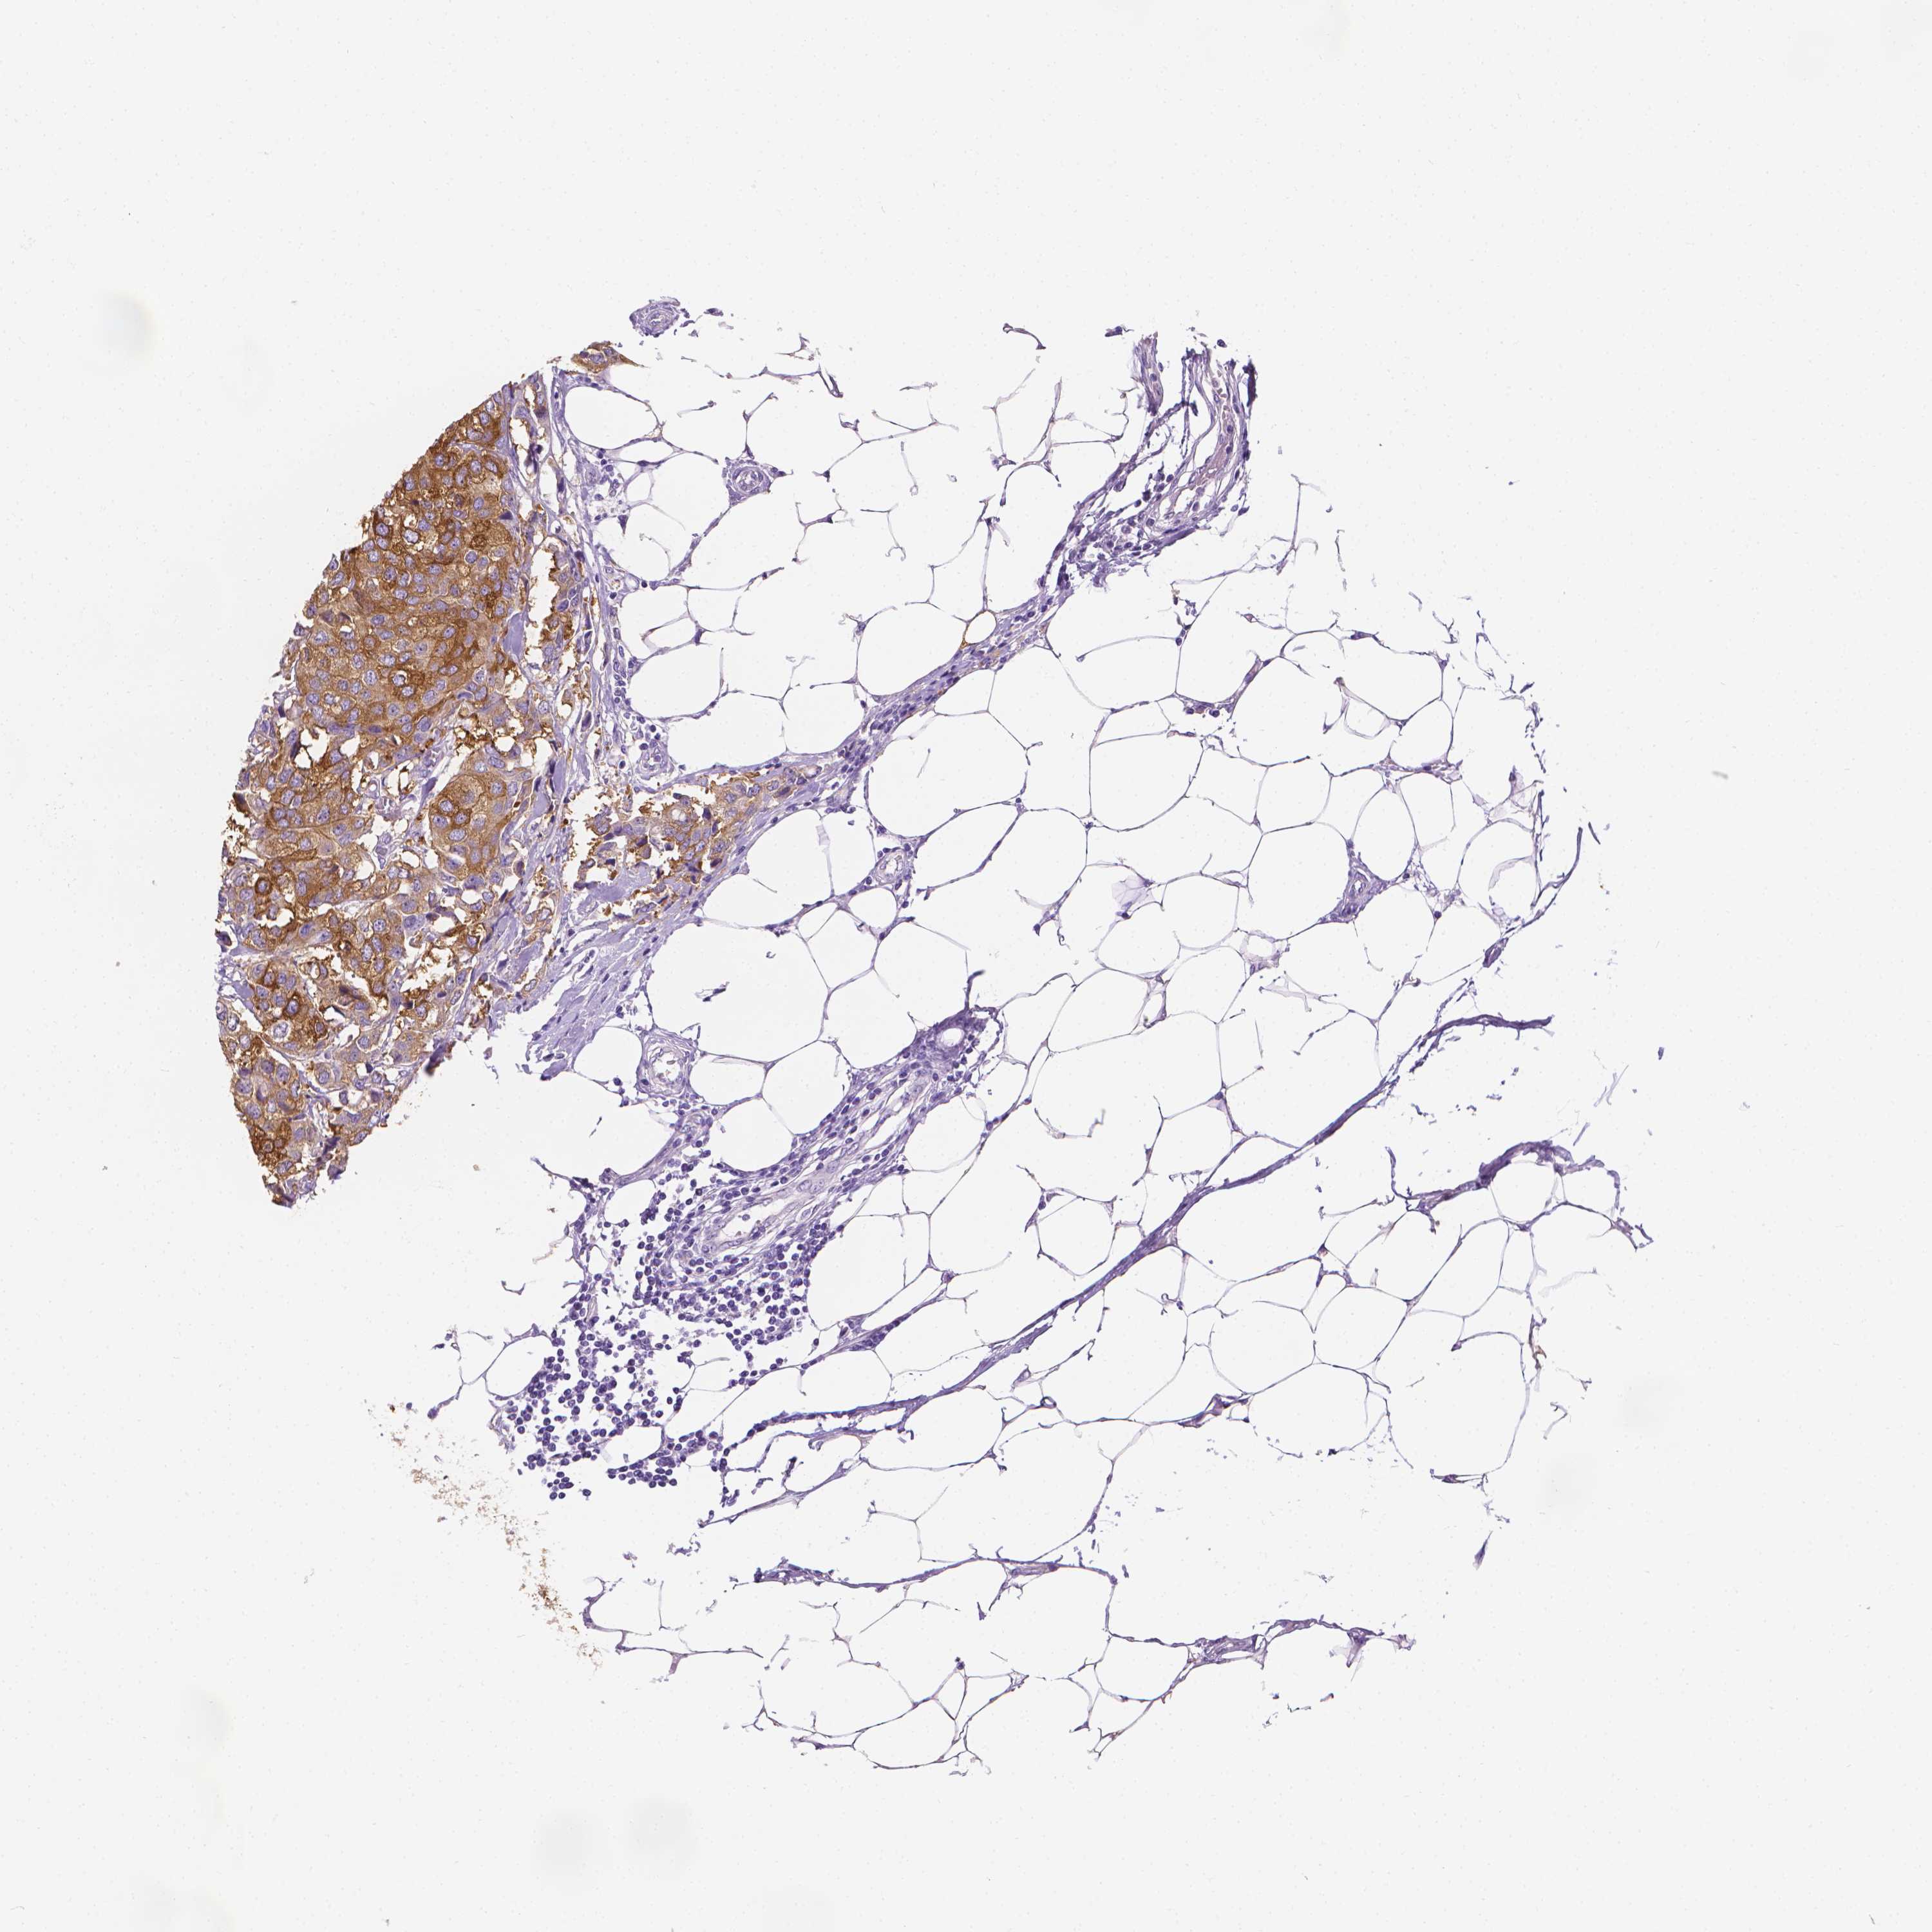

CANCER BREAST CANCER Show tissue menu

BRCA TCGA BRCA VALIDATION PROTEIN EXPRESSION